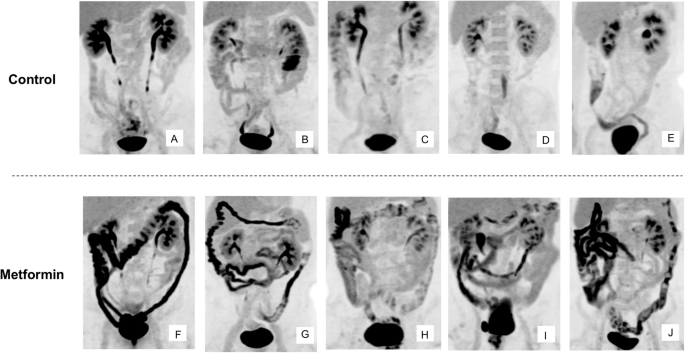

We next attempted to quantify the intraluminal excretion of FDG by developing a bioimaging system based on PET-MRI. We adopted imaging sequences of magnetic resonance enterography (MRE)19 to generate three-dimensional (3D) images of the entire intestinal tract (Supplementary Movie 2). We then superimposed the [18F]FDG PET images onto the 3D MRE images to obtain information on the 3D distribution of radioactivity. We termed this imaging sequence PET-MRE. We performed PET-MRE for individuals with T2D treated or not treated with metformin and evaluated the absolute amount of radioactivity in each part of the intestine with discrimination between the wall and lumen. The characteristics of these study subjects and corresponding maximum intensity projection (MIP) PET images are shown in Table S5 and in Fig. 2, respectively.

Images obtained at 60 min after [18F]FDG injection are shown for individuals with T2D not treated (A–E) or treated (F–J) with metformin.